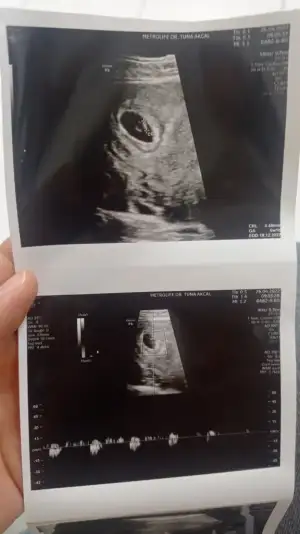

ben bile anlamadığım halde yüzünde kız güzelliği gördüm :)Merhabalar :) Biz 29. Haftaya girdik ama hala emin olamadı doktorum. En son 13 haftalik fotoğrafı var bende ve karından çekildi. Sizin de fikrinizi merak ettim bir bakar mısınız![]()

Aynı mesajı dün tam paşa bugün prenses gibi diye cevaplamışsın canımKuzu prenses gibi duruyor sen ne hissediyorsun